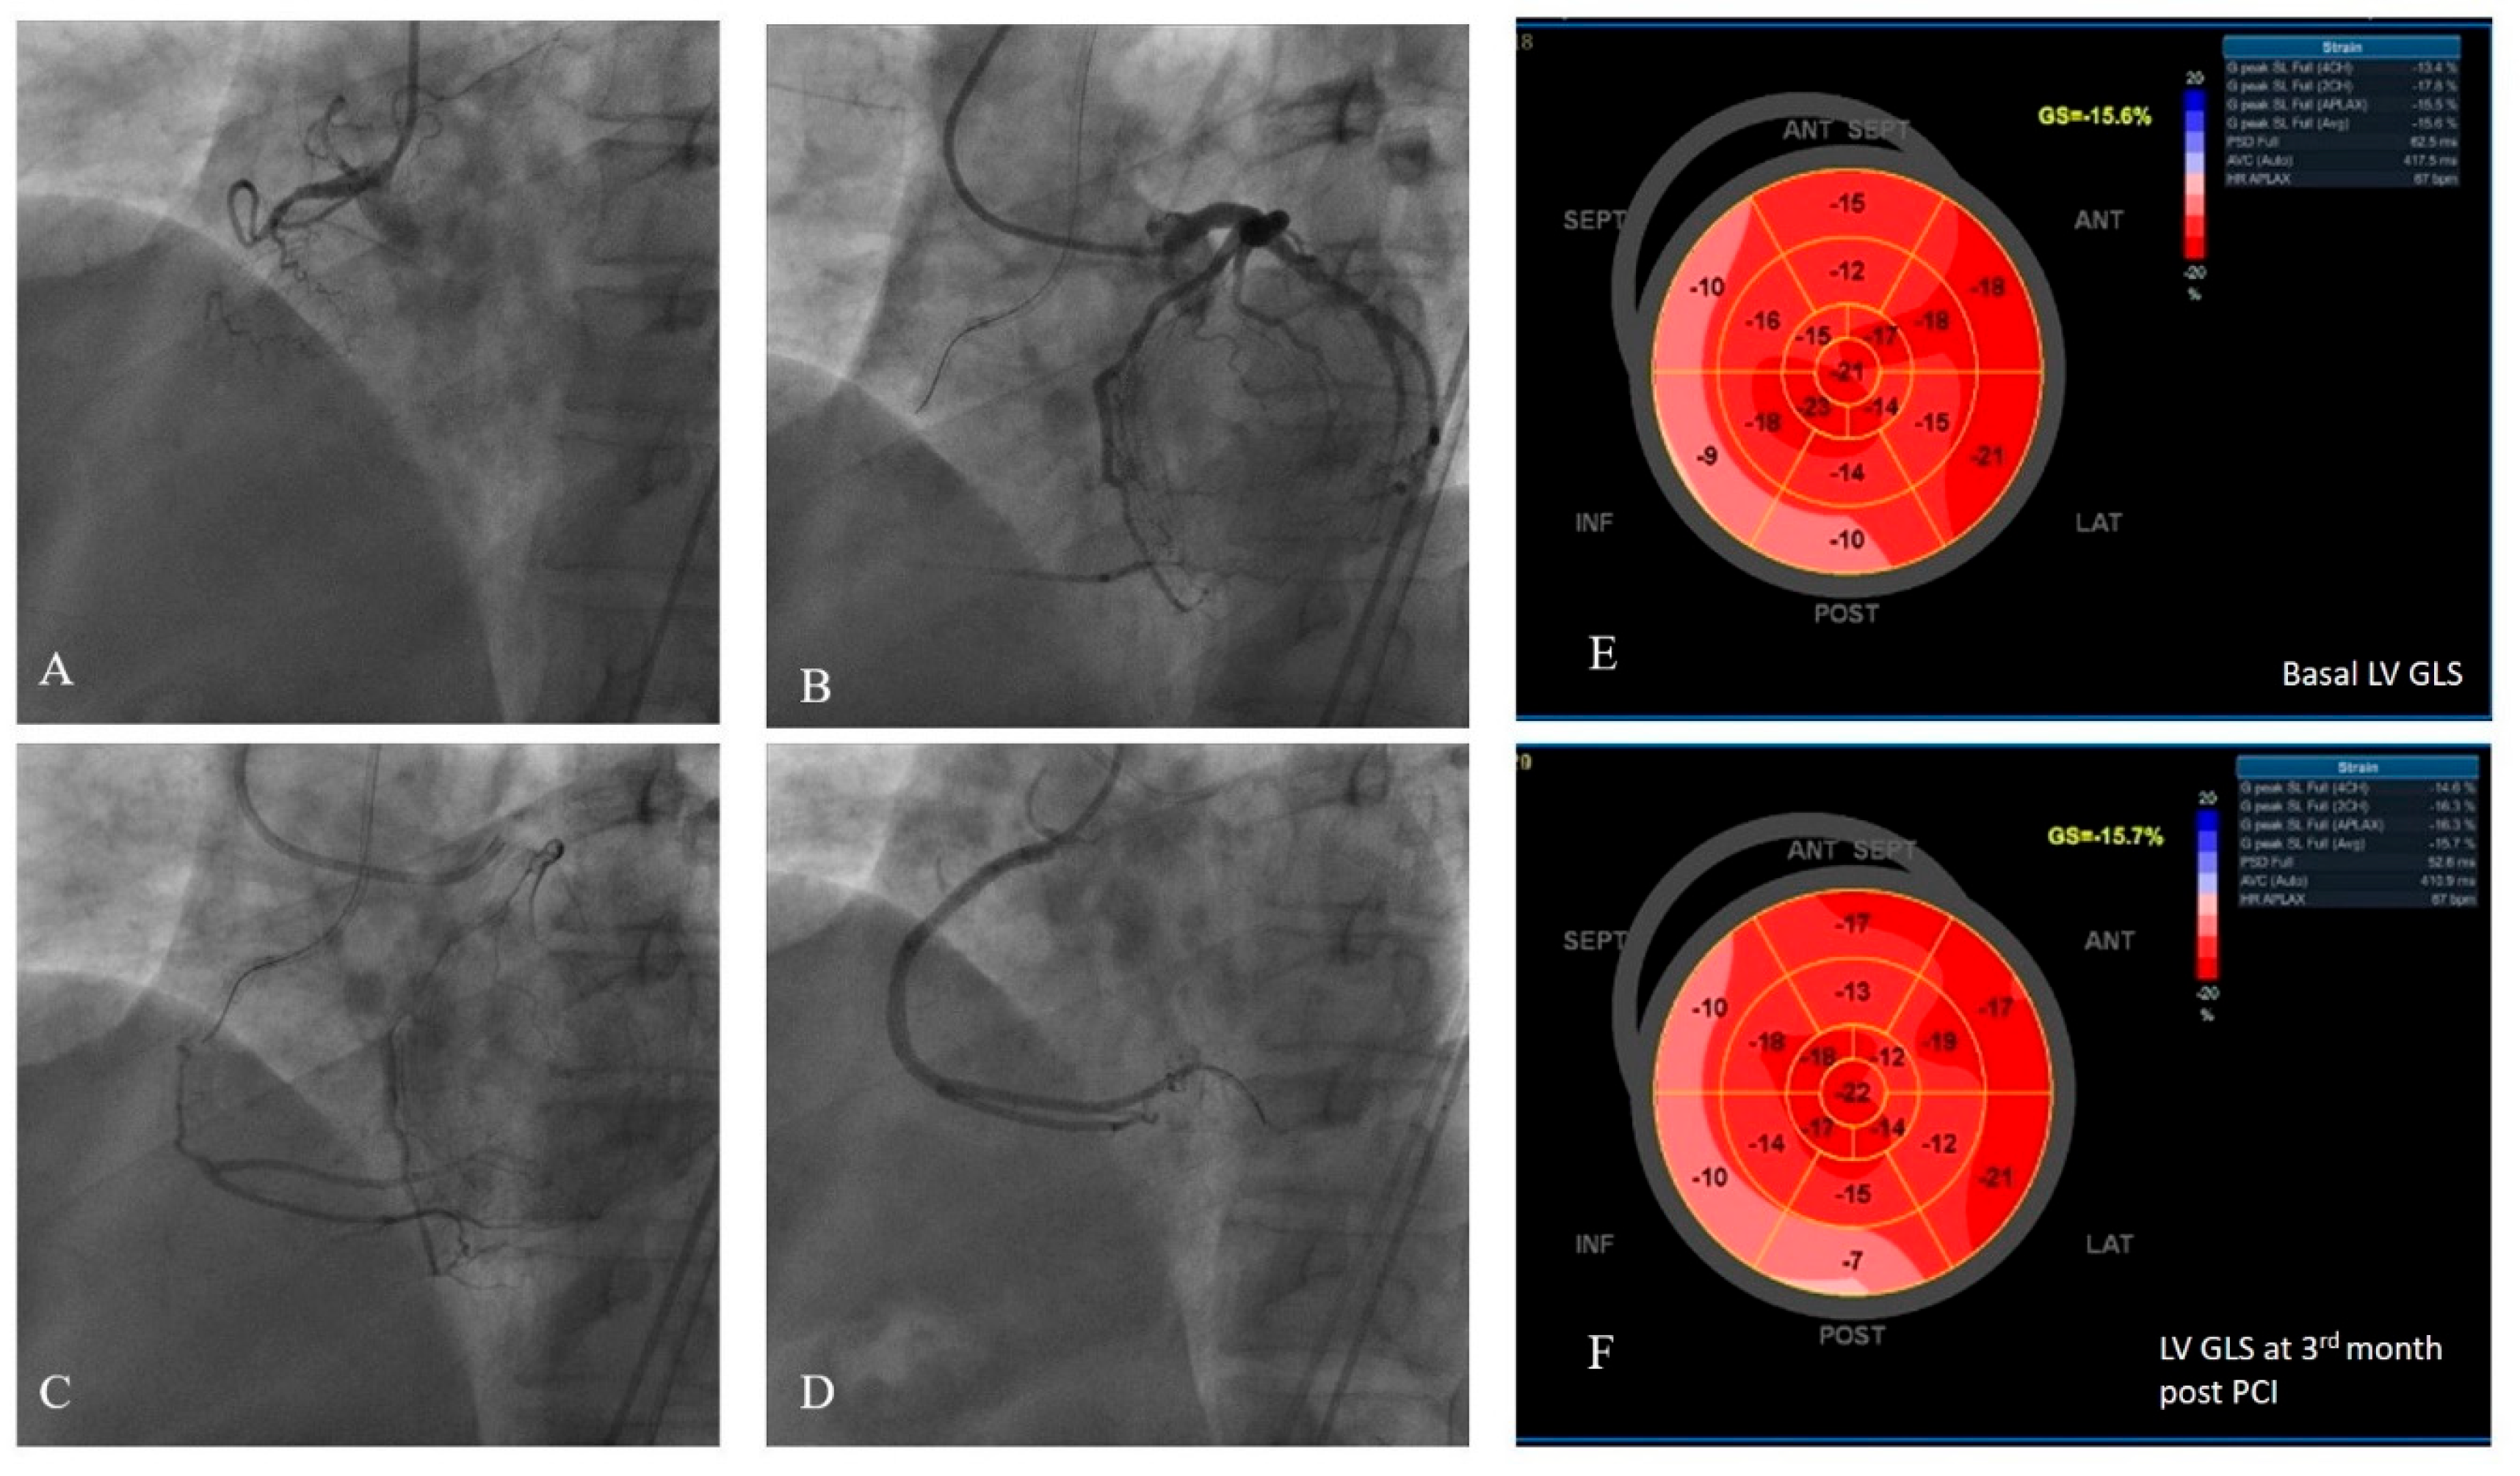

Coronary Angiography: An interventional cardiologist performed coronary angiography according to standard procedures. Following diagnostic coronary angiography, all patients underwent heart team discussion. Patients with typical anginal symptoms under OMT were enrolled directly if they had no exclusion critera. For other symptomatic patients, MPS was ordered to detect ischemia in the target area, since these patients presented with atypical angina or symptoms of effort intolerance, further clarification was required. Patients who were indicated for revascularization by the heart team underwent PCI, performed by experienced interventional cardiologists using femoral access. In accordance with their expertise, the medical team recanalized the CTO, using specialized wires, balloons, and microcatheters. All patients were revascularized with drug eluting stents. Preoperative, perioperative and follow-up medical management, including the antiplatelet regimen, adhered the current guidelines [18]. Angiographic success was defined as achieving a final angiographic residual stenosis of less than 20% by visual estimate and TIMI III flow following the implantation of stents [19]. Two blinded interventional cardiologists classified coronary collaterals according to Cohen-Rentrop classification, which was graded as follows: grade 0= no visible collaterals, grade 1= the filling of the side branch via collateral vessels without visualization of the epicardial segment, grade 2= the partial filling of the epicardial coronary artery, and grade 3= the complete filling of the epicardial coronary artery [20]. Enrolled patients were classified as WD (grades 2 and 3) and poor (grades 0 and 1) coronary collateral groups [21]. Figure 1 presents an example study patient who had WD collaterals and had successful CTO recanalization, followed-up with consecutive LV GLS measurements recorded at baseline and at the third month.

Figure 1. An example of a study patients’ LV GLS strain and coronary angiography views. (A) Chronic total occlusion of RCA. (B-C) Dual injection demonstrated the presence of grade 3 collateral circulation from the left coronary arteries to the RCA. (D) The RCA was successfully wired, two drug-eluting stents were implanted, and TIMI 3 flow was demonstrated.(E) Pre-PCI average LV GLS was measured to be -15,6%. (F) Post-PCI third month LV GLS was measured to be -15,7%.LV GLS: left ventricular global longitudinal strain.

LV GLS: left ventricular global longitudinal strain, RCA: right coronary artery, PCI: percutaneous coronary intervention